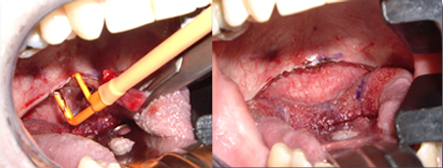

適用于細(xì)微、精細(xì)的切割如頭頸部,敏感部位皮膚的切割。

可實(shí)現(xiàn)切割,凝血同步。

適合于要求良好止血的切割。

愛(ài)爾曼國(guó)際有限公司(Ellman International, Inc.)總部位于美國(guó)紐約市,是一家專門生產(chǎn)高頻射頻電波刀和相關(guān)附屬產(chǎn)品的專業(yè)公司。其產(chǎn)品代表著當(dāng)前先進(jìn)的射頻電波手術(shù)技術(shù),產(chǎn)品銷往世界各地,被世界著名醫(yī)療機(jī)構(gòu)廣泛采用。大量發(fā)表在世界著名學(xué)術(shù)刊物 的科學(xué)研究和臨床實(shí)踐的文章,以及大量醫(yī)學(xué)專業(yè)的教科書(shū)都表明愛(ài)爾曼高頻射頻電波刀是當(dāng)前臨床應(yīng)用中對(duì)組織損傷最小、用途最廣泛、性能價(jià)格比最好、最具有市場(chǎng)競(jìng)爭(zhēng)力的醫(yī)療設(shè)備之一。愛(ài)爾曼產(chǎn)品的獨(dú)特性能和優(yōu)秀質(zhì)量在國(guó)際享有崇高的聲譽(yù),其銷售量一直在國(guó)際市場(chǎng)名列前茅。在美國(guó)的銷量超過(guò)萬(wàn)臺(tái),在日本的銷量已經(jīng)超過(guò)5,000臺(tái)。愛(ài)爾曼國(guó)際有限公司在中國(guó)設(shè)立有常駐辦事機(jī)構(gòu)提供市場(chǎng)宣傳、技術(shù)支持、業(yè)務(wù)培訓(xùn)、公共關(guān)系、售后服務(wù)等業(yè)務(wù)。